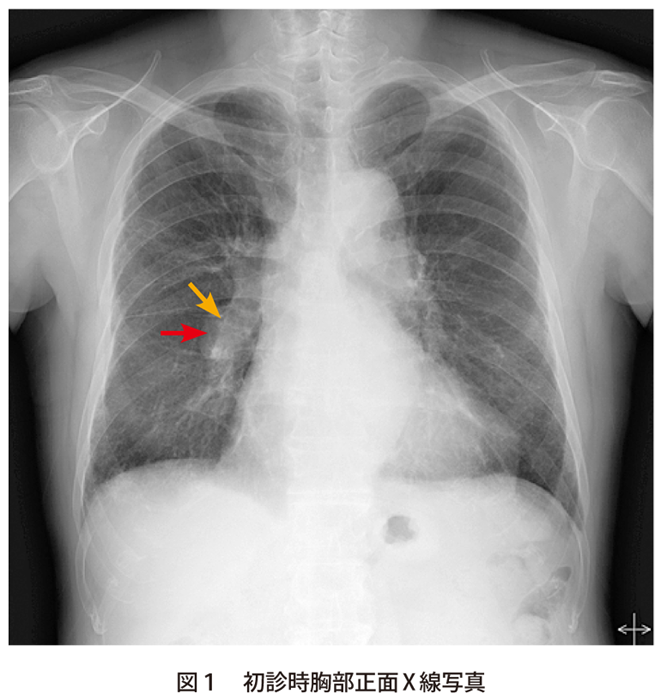

解答 解説 息切れを訴える70歳代男性 実践 画像診断q A 羊土社 レジデントノート 実践 画像診断q A 羊土社 レジデントノート 羊土社